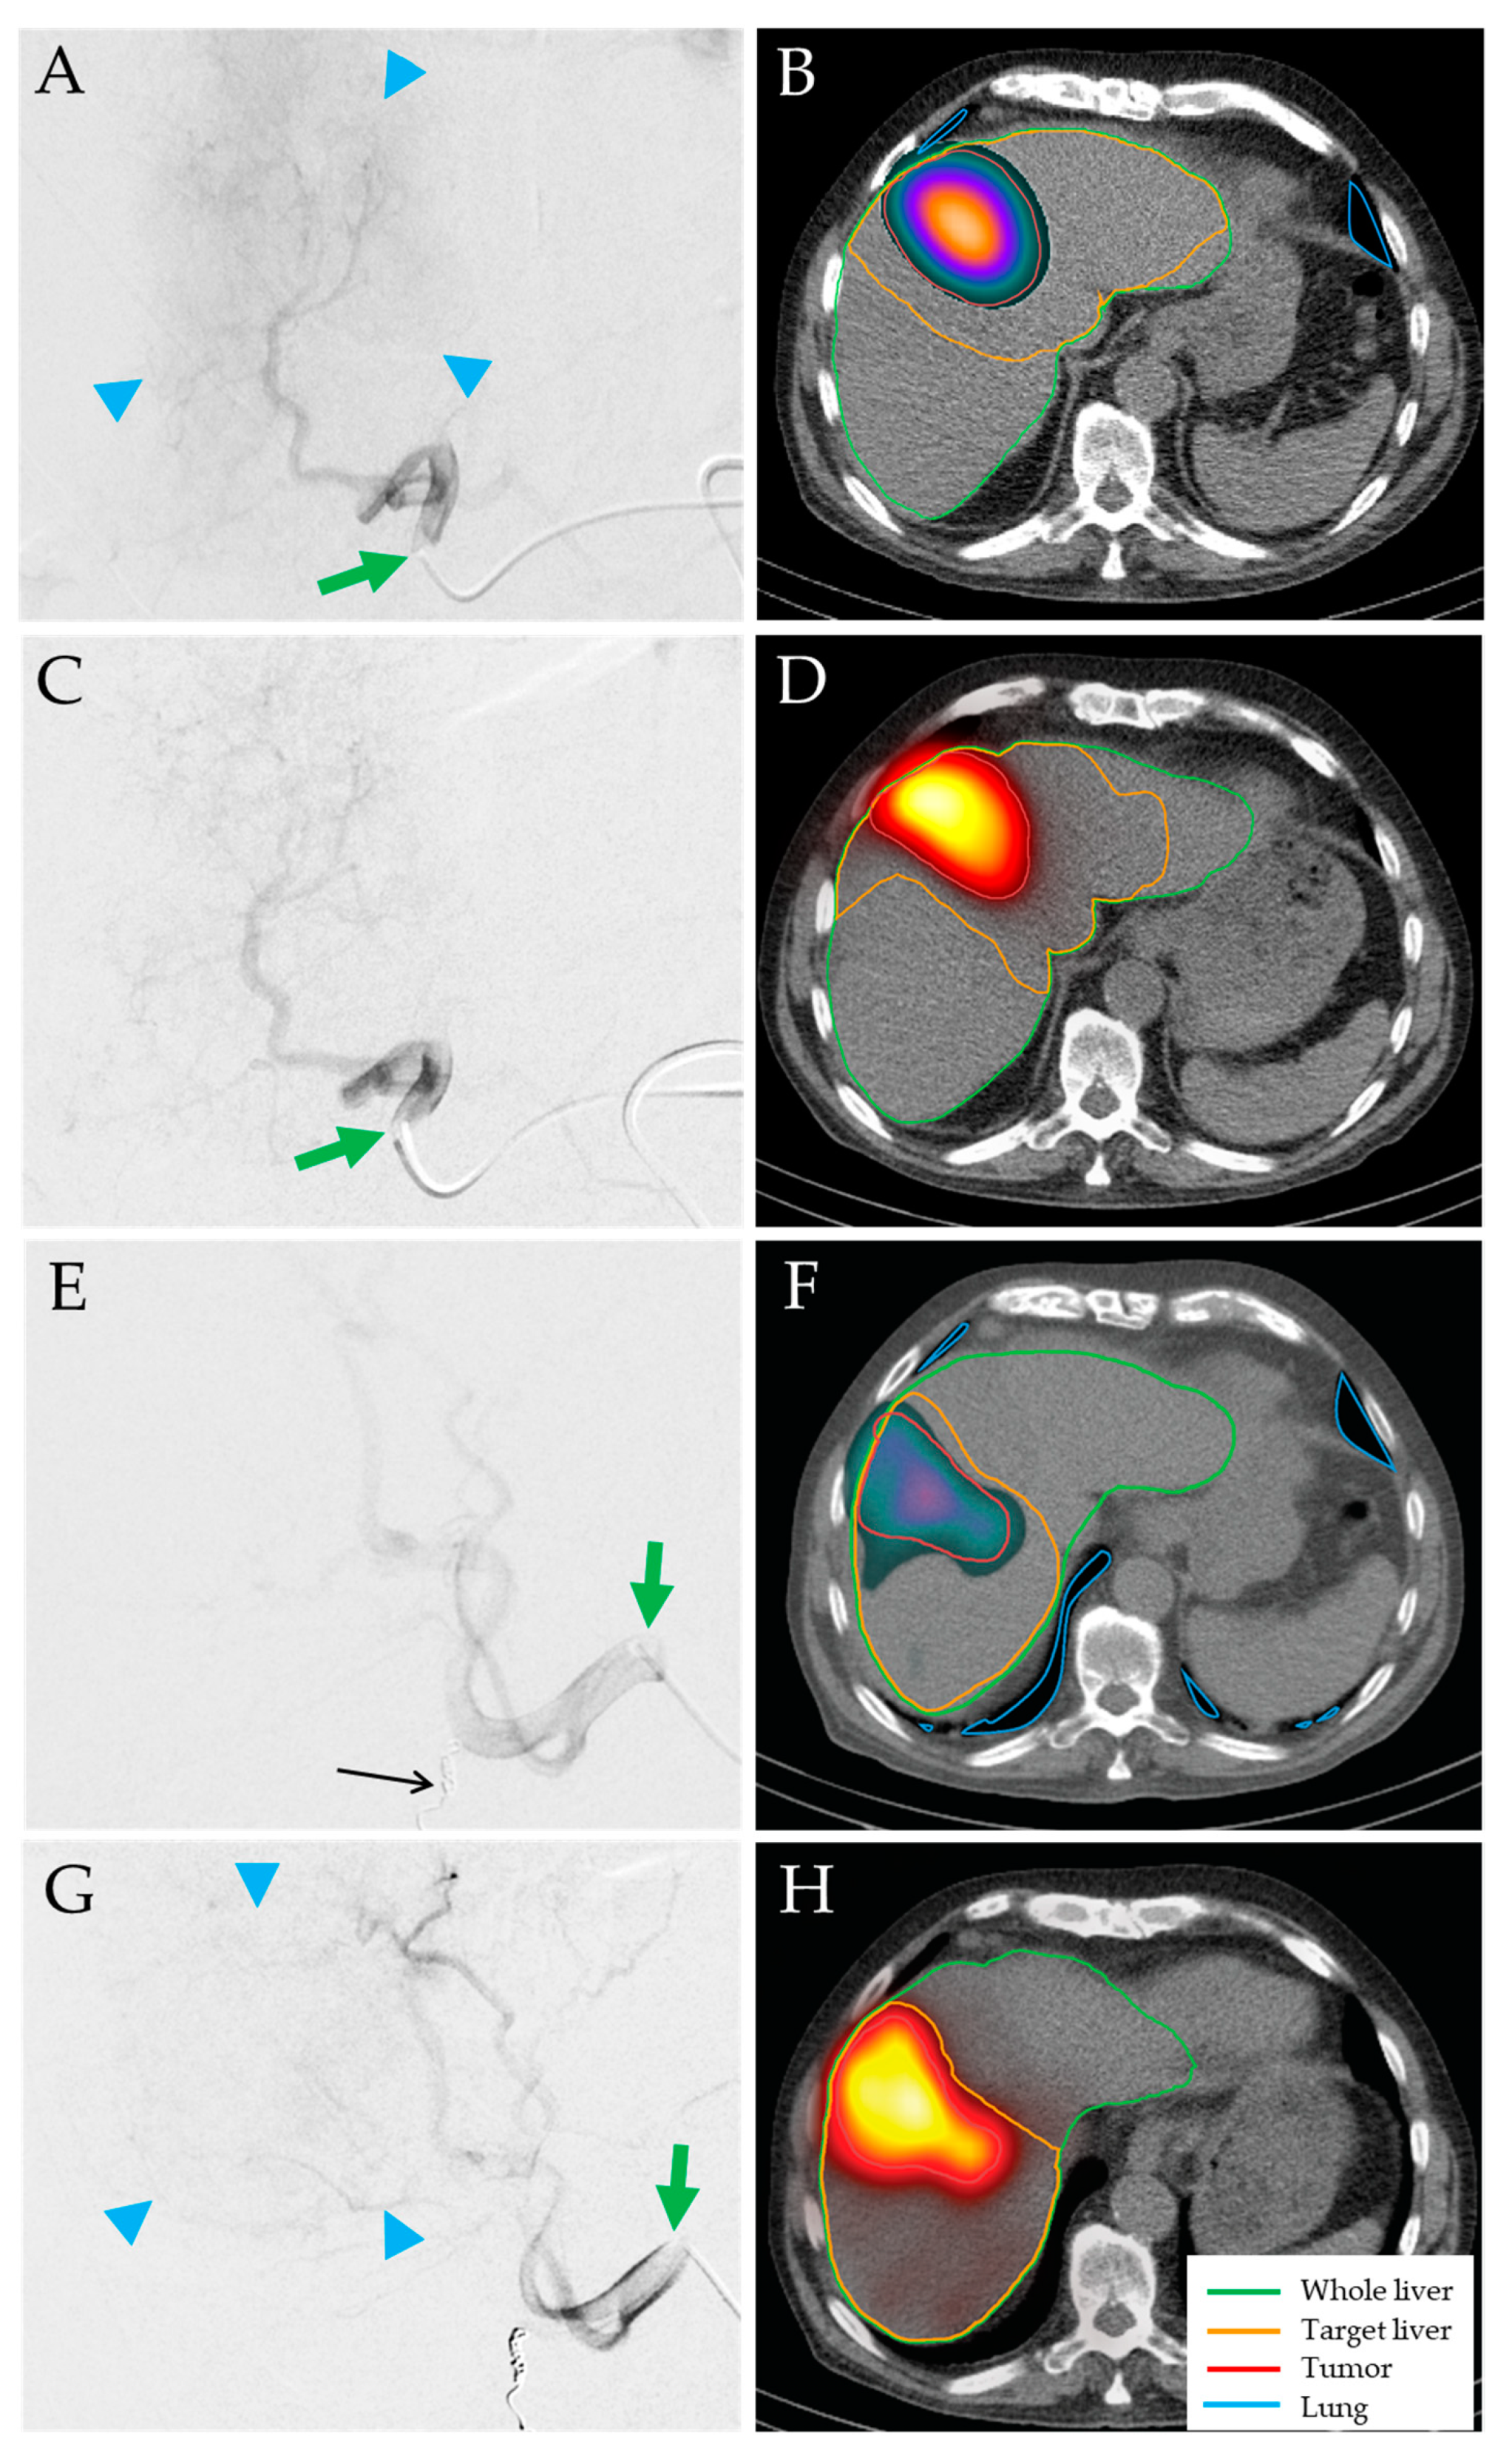

- A 58-year-old man with HCC stage II and severe liver cirrhosis (BCLC D, ALBI grade 3, Child–Pugh score C11, moderate ascites, bridging-to-transplant 166Ho-TARE of liver segment II, target 14% of whole liver, healthy target/tumor doses: 59 Gy/119 Gy). The patient was discharged as planned, but readmitted to hospital with acute or chronic liver failure (ACLF) grade 3, pneumonia, and sepsis. The Child–Pugh score deteriorated to C13. The patient died 6 days after 166Ho-TARE.

- A 74-year-old man with HCC stage II and liver cirrhosis (BCLC B, ALBI grade 2, Child–Pugh score A6, no ascites, palliative 166Ho-TARE of left liver lobe, 43% of whole liver, healthy target/tumor doses: 49 Gy/148 Gy). The follow-up at three months showed PR of the tumor, but moderate ascites (Child–Pugh score B8). The liver function deteriorated rapidly. The patient died 3.2 months after 166Ho-TARE.

- A 69-year-old man with HCC stage IIIB and liver cirrhosis (BCLC B, ALBI grade 2, Child–Pugh score B7, moderate ascites, palliative 166Ho-TARE of right liver lobe, target 55% of whole liver, healthy target/tumor doses: 41 Gy/114 Gy). The follow-up at three months showed PD in both liver lobes with macrovascular involvement and a Child–Pugh score of B8. The patient died 4.0 months after 166Ho-TARE.

- A 65-year-old man with HCC stage II in the liver segment IV, maximum diameter 19 cm compressing the portal vein and liver veins, no liver cirrhosis (BCLC C, ALBI grade 3, Child–Pugh score B8, no ascites, palliative 166Ho-TARE of the liver segment IV, 28% of whole liver, healthy target/tumor doses: 42 Gy/88 Gy; tumor not completely perfused). The follow-up at three months showed PR of the tumor and tumor progression in adjacent liver segments. Four months after 166Ho-TARE, the liver function deteriorated rapidly (Child–Pugh score C13). The patient died 5.6 months after 166Ho-TARE.